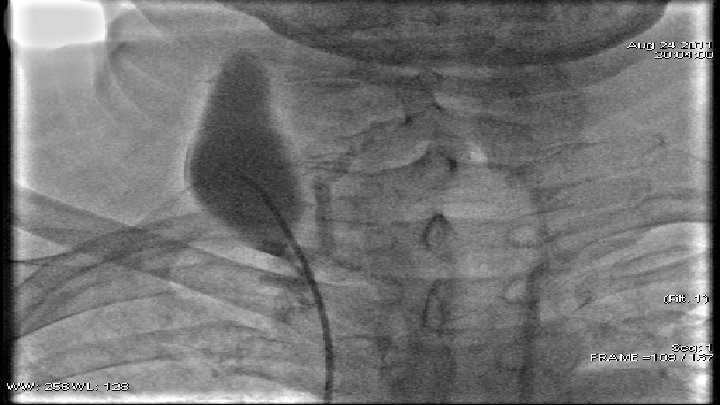

Case 2 q 59 y. o. patient q June 2011 - diagnosed with small-cell lung cancer q August 2011 - angiographic data of subtotal occlusion of VCS. q. PTA – baloon dilatation and stent implantation